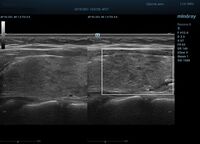

HD Scope позволяет достигать поразительной разрешающей способности выбранной зоны сканирования, при этом улучшая как детализацию, так и контрастность изображения. Помимо пространственного разрешения мы получаем преимущество и по разрешению во времени. Прибор получает огромное количество нативных изображений практически одновременно, и при сборе итоговой картины не происходит смещения объекта под датчиком, а значит и нет размывания изображения. Все участки раздела фаз, каждый контур образования теперь видны, мы все ближе к идеальной картинке.

Как он работает? Особенностью платформы ZST+, на которой построены приборы Mindray Resona, является так называемое многолучевое сканирование. В отличие от обычного датчика, который получает изображение в виде прямого эхо, датчики приборов этой серии проводят многолучевое сканирование каждым элементом с огромной скоростью, получая огромное количество данных. Затем происходит сложная постобработка и сбор из множества «многолучевых» снимков идеальной картинки.

Вторая особенность ультразвуковых машин данной линейки — это изменение расчетных констант распространения ультразвука, таким образом прибор перебирает для каждой ткани свои значения скоростей волны и пересчитывает каждую точку, делая менее выраженным поглощение по глубине. Эти особенности позволили использовать без фокусные технологии сканирования. Функция HD Scope позволяет использовать эти ресурсы для исследование небольшой области, значительно увеличивая качество изображения.